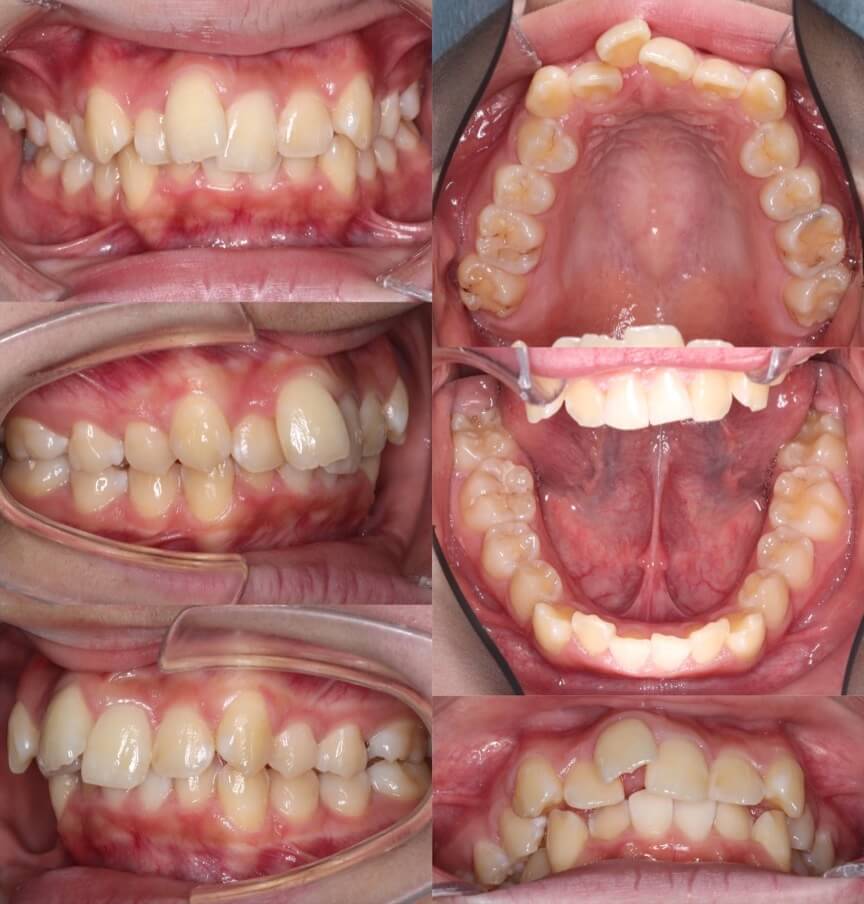

高校生女性・マウスピース型矯正装置・上抜歯

<顔のビフォーアフター>

<症例概要>

主訴:出っ歯

年齢・性別:大学生女性

住まい:千葉県船橋市

症状:上顎前突・開咬・シザーズバイト

治療方針:抜歯空隙閉鎖・IPR

治療装置:マウスピース型矯正装置(アライナー装置)+セクショナルワイヤー

抜歯:上左右第一小臼歯(計2本)

治療期間:2年(1週間交換)

アライナー枚数:41+23+12ステージ

リテーナー:上下フィックスタイプ+クリアタイプ

治療費用:990,000(税込)

代表的副作用:痛み・治療後の後戻り・歯根吸収・歯髄壊死・歯肉退縮

▶︎その他の副作用

【治療シミュレーション】

上の抜歯スペースを順次的に閉鎖していきます。下の一番奥歯はマウスピースで歯をつかめないためワイヤー装置を併用しています。

※マウスピース型カスタムメイド矯正歯科装置は完成物薬機法対象外の矯正装置であり、医薬品副作用被害救済制度の対象とはならない可能性があります。

シザーズバイトになっている下の第二大臼歯は、半分以上歯茎が覆っておりマウスピースでつかむには面積が足りないため、部分的にブラケット装置(セクショナルワイヤー)を併用しました。このように効率性と治療期間の兼ね合いをみてワイヤー矯正装置を併用することはあります。